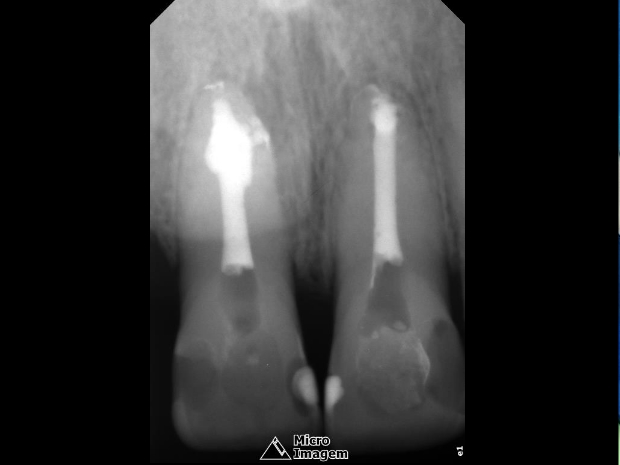

O mesmo relatava histórico de trauma dental na infância, sendo que previamente foi submetido a uma intervenção de urgência no elemento 21 por outro profissional, visto que se apresentava com edema e dor na região apical. Pela presença de fístula nesta região, foi realizado rastreamento na mesma, sendo a mesma oriunda do elemento dental 21 (figuras 2 e 3).

Após a abordagem inicial do paciente, o mesmo foi anestesiado e procedeu-se à confecção do isolamento absoluto. Posteriormente, o acesso coronário foi realizado, onde se constatou clinicamente a necrose pulpar de ambos os dentes. Foi realizada uma penetração desinfetante crown-down empregando como agente irrigador NaOCl a 5%, sendo a odontometria realizada pelo método radiográfico, devido a inviabilidade de emprego de um localizador foraminal nestas condições anatômicas, podendo influenciar em sua precisão (figura 4).

- Figura 2

- Figura 3

- Figura 4